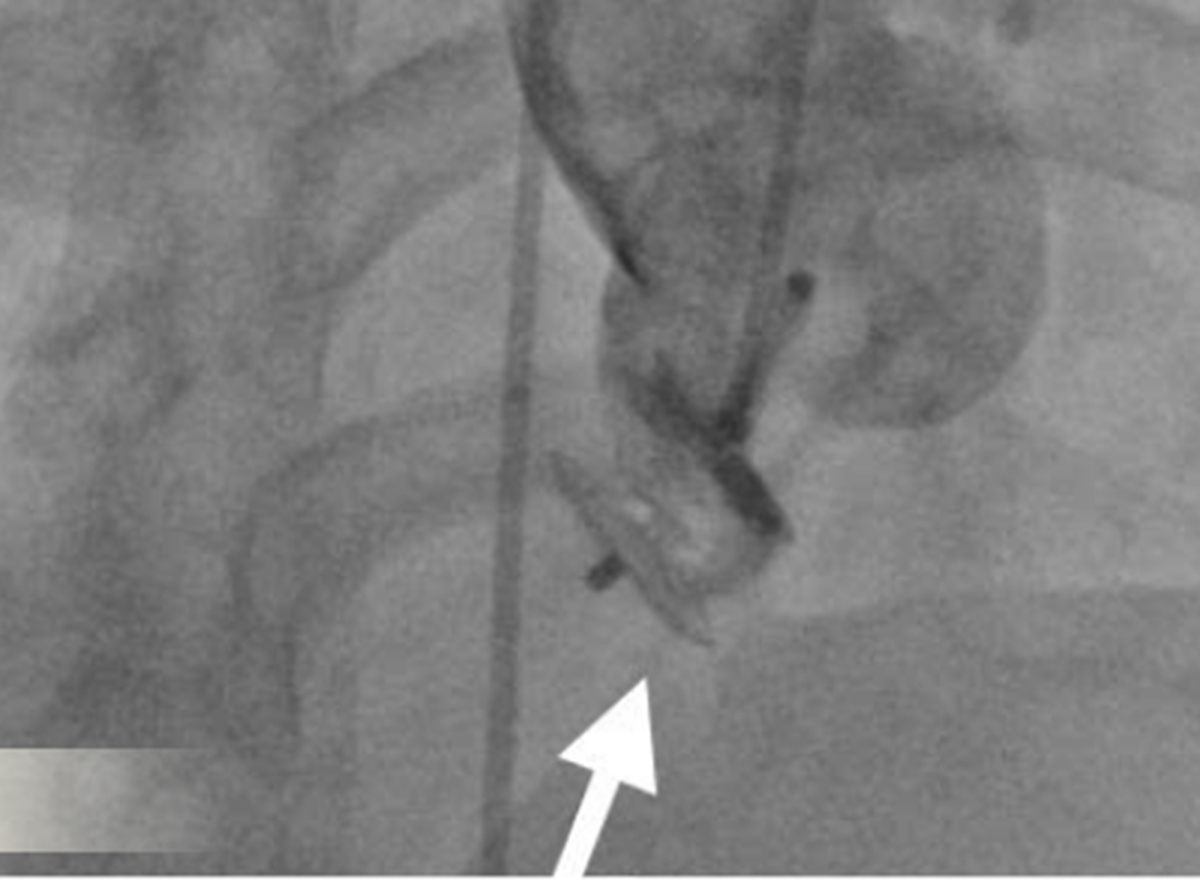

Bác sĩ can thiệp bít kín thành công bằng dù xoang Valsalva

Thông qua siêu âm tim qua thực quản, các bác sĩ đã xác định chính xác vị trí lỗ vỡ của xoang Valsalva, đo được kích thước của lỗ vỡ; cũng như đánh giá khoảng cách từ vị trí vỡ đến lá van động mạch chủ.

Những thông số này có ý nghĩa quyết định, không chỉ giúp đánh giá mức độ nguy hiểm của bệnh lý mà còn là cơ sở để lựa chọn phương pháp điều trị tối ưu, an toàn, tránh ảnh hưởng đến các cấu trúc tim quan trọng như van động mạch chủ và động mạch vành.

Ngay sau can thiệp, người bệnh cải thiện triệu chứng rõ rệt, gần như không còn cảm giác đau ngực và khó thở. Người bệnh có thể đi lại, sinh hoạt bình thường ngay trong ngày, không cần trải qua quá trình hồi sức kéo dài như phẫu thuật tim hở. Sau 1 ngày theo dõi, người bệnh ổn định hoàn toàn và được xuất viện.